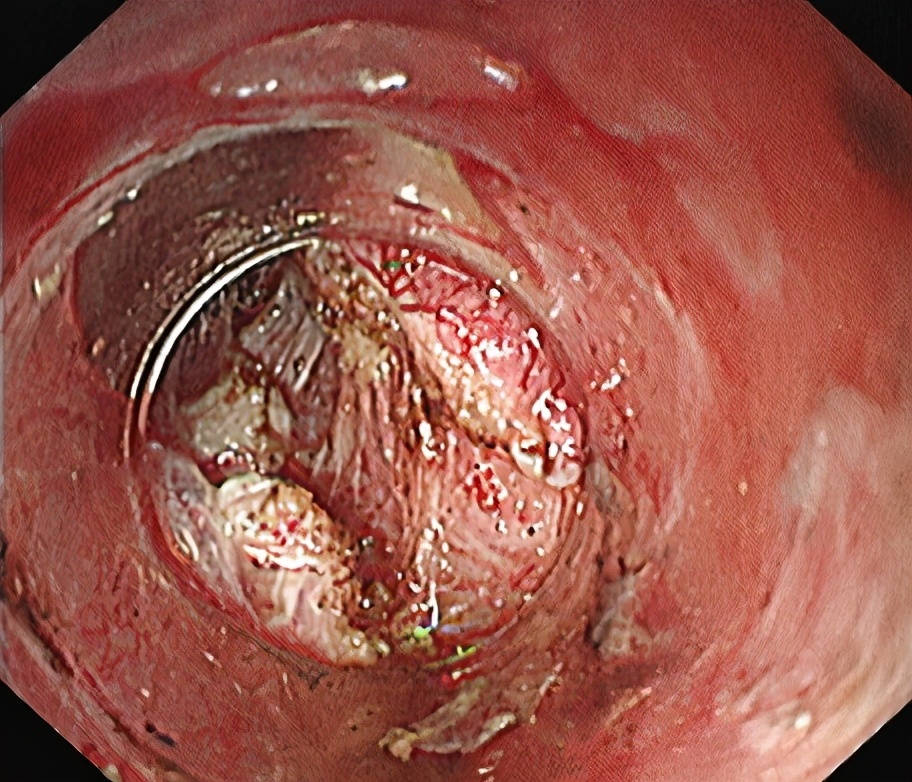

环形肌切开。

退出“隧道”前观察,钛夹关闭黏膜层切口。